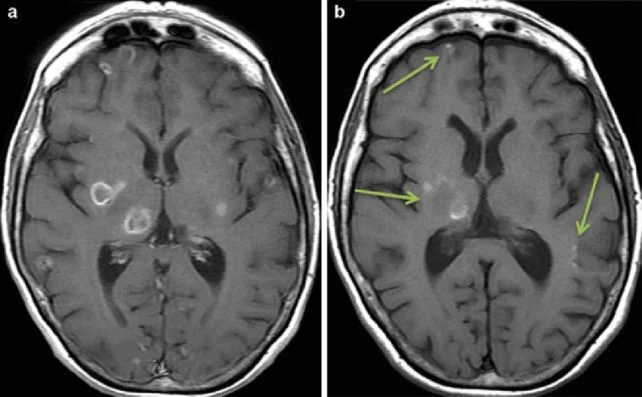

T. gondii известен своей способностью изменять поведение хозяев – как в лучшую, так и в худшую сторону. Этот паразит предпочитает селиться внутри клеток, особенно в нейронах, преодолевая гематоэнцефалический барьер. Оказавшись внутри, простейшее может оставаться там десятилетиями, не вызывая явных симптомов.

Оказалось, что зараженные клетки не только производили меньше везикул, но и их содержимое отличалось от нормы. Поскольку EV участвуют в передаче сигналов между нейронами и астроцитами, это привело к каскадному эффекту: изменилась экспрессия генов в астроцитах, что вызвало увеличение выработки определенных иммунных маркеров и снижение уровня транспортера, удаляющего избыток глутамата из мозга.

Повышенный уровень глутамата связан с такими проблемами, как судороги и повреждение нейронов – осложнения, которые наблюдаются при тяжелых формах токсоплазмоза. Это говорит о том, что влияние T. gondii может быть серьезнее, чем считалось ранее.